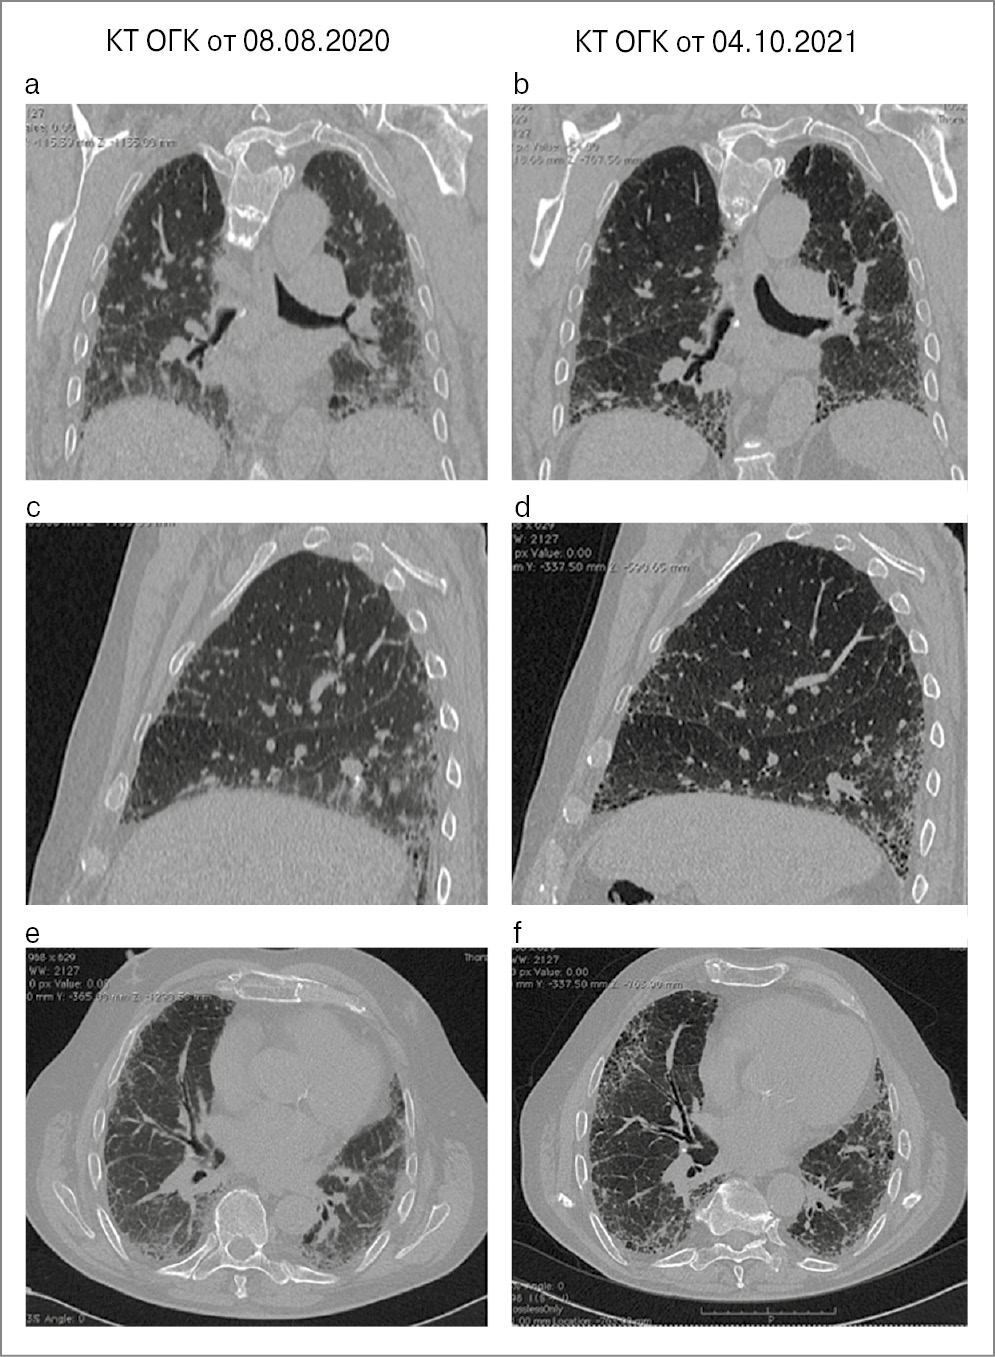

КТ ОГК (рис. 23): КТ-паттерн вероятной ОИП – без динамики по сравнению с августом 2020 г.

Рис. 23. КТ ОГК пациента Х от 08.08.2020 в сравнении с КТ ОГК от 04.10.2021.

КТ ОГК (рис. 24): КТ-паттерн вероятной ОИП, отрицательная динамика в виде увеличения количества тракционно расширенных бронхиолоэктазов.

Рис. 24. КТ ОГК пациента Х от 08.08.2020 в сравнении с КТ ОГК от 05.04.2023.